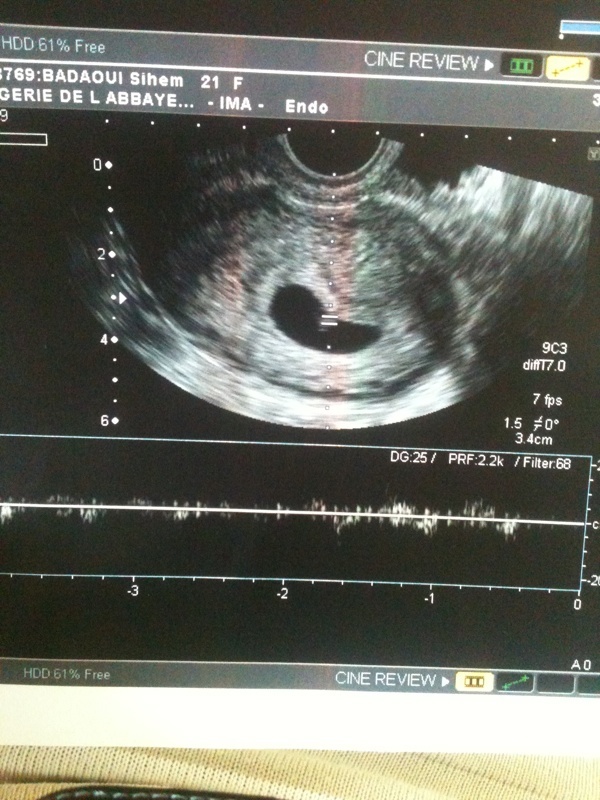

Date dernière règles: 1avril2012

Âge théorique de la grossesse: 9sa

L'examen met en évidence un utérus gravide contenant un sac ovulaire unique sans signe de décollement du sac contenant un embryon unique avec activité cardiaque perçue

La longeur cranio caudale de l'embryon est de 2,33 mm. L'aspect correspond a 5semaine et demie d'aménorrhée .

Donc on gros ji comprend rien sachan que ya 5 semaine g fait une prise de sang ki me diser plus de 3semaine!

Peut être qu'il a eu du mal a démârer hâte d'être le 13 pour une ôtre échos.

La seul photo ke g eu